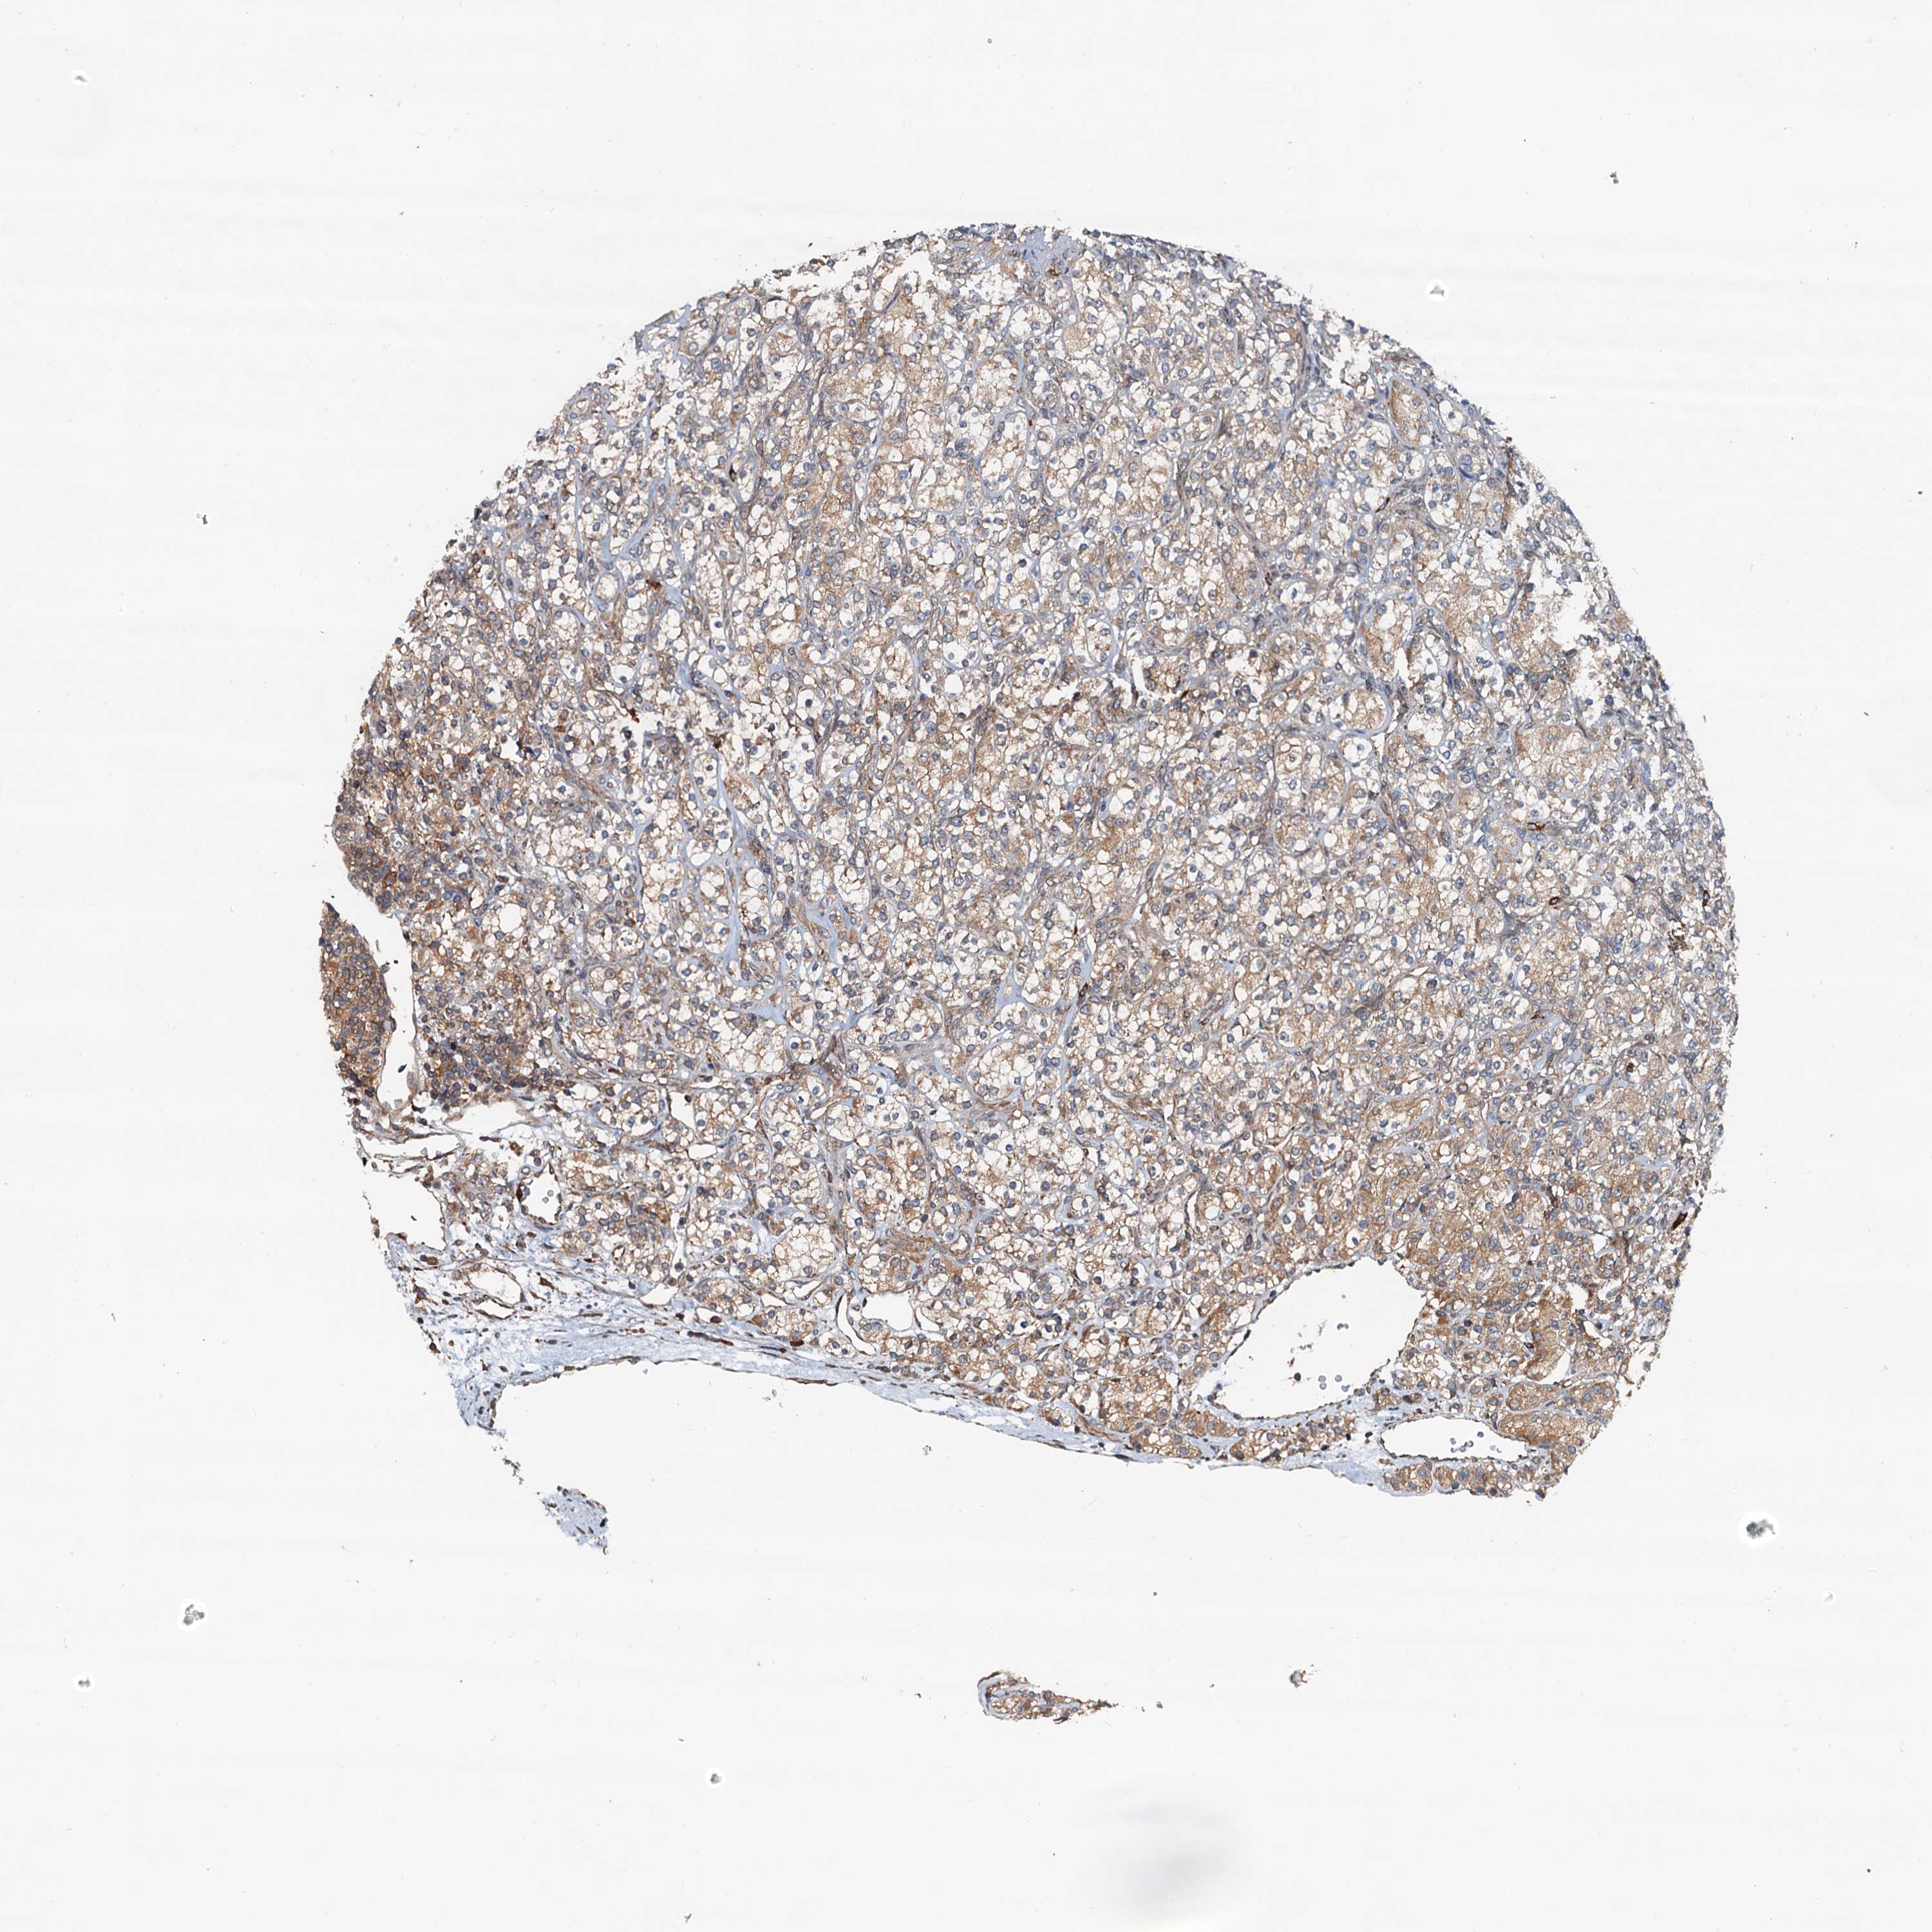

CANCER RENAL CANCER Show tissue menu

KICH TCGA KIRC TCGA KIRC VALIDATION KIRP TCGA PROTEIN RCC CPTAC PROTEIN EXPRESSION